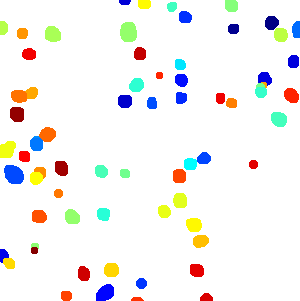

Figure 6 shows how our method segments the nuclei step by step. The color variety is well controlled by the color normalization procedure. The prediction result shows clear nuclear areas and nucleus boundaries. In the final segmentation result and ground truth image, each nucleus is represented by a different color.

First, We test our method on the MOD dataset. Unfortunately, the dataset publicly provided online doesn’t explicitly divide the whole dataset into the training set and test set. We do not know which image belongs to the training set exactly as introduced in their paper [22]. To make a fair comparison, we randomly select 16 images from breast, liver, kidney and prostate. Then we combine the remaining 8 images of these four types and the 6 images from bladder, colon and stomach to build the test images. 12000 patches are randomly extracted from 12 training images to train our model. To eliminate the bias caused by random selection, 5 different training sets and the corresponding test sets are randomly generated. Then the model is trained and tested on the 5 pairs of training set and test set separately. All of the models are trained for 300 epoch in 7.5 hours. For testing, the stride of overlapped patch extraction is set to 64. The quantitative comparison is listed in Table I, which demonstrates that our method outperforms the state-of-the-art method CNN3 as reported in [22] in terms of both F1 score and Dice’s Coefficient. Moreover, it shows that the under-segmentation error is much more significant than over-segmentation error and it achieves a balance between the false detection error and missing detection error. Figure 7 shows a visual comparison between our method and [22]. As shown in the sample images, our segmentation result has fewer false negatives and higher accuracy in terms of nuclei boundaries than [22]. Our method is not only more accurate but also much faster. It takes about 5 seconds to predict a 1000 * 1000 image by one Nvidia Titan X GPU and the time used for post-processing is less than 0.1 seconds. Given the same hardware environment and test images, [22] takes about 4 minutes to predict one image and 80 seconds to do the post-processing. Additionally, a 10-folder cross-validation is performed to validate our method. The result is shown in Table I NB model *.